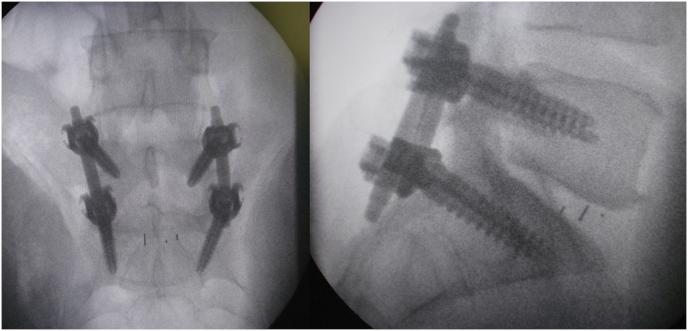

The technique facilitates bilateral canal enlargement through unilateral approach and provides accessibility to the contralateral foramen for decompression with perfect exposure and allows instrumentation through the lateral window with no muscle destruction.